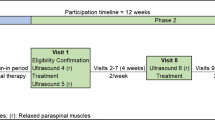

This work was a repeated-measures reliability and discriminative validity study, conducted in accordance with the Guidelines for Reporting Reliability and Agreement Studies (GRRAS)34. The study was part of a larger project assessing neuromotor associations of the TLF that was prospectively registered with the German Clinical Trials Register (DRKS00027074). The study has been reviewed and approved by the ethical committee of the Diploma Hochschule, Germany (Nr.1014/2021), has been carried out in accordance with the declaration of Helsinki and has obtained informed consent from the participants35.

The first rater sonographically recorded the transverse process of L1. Subsequently, the transducer was moved laterally until the junction of the latissimus muscle and the TLF was visible. The transducer was rotated laterally and caudally until the fibers of the latissimus muscle were aligned in parallel and the reflective tape was placed on the skin32. The rater then performed the first measurement during TET in the starting and ending positions (t0). Afterwards, the transducer and the tape were removed without leaving any visible marks on the skin and a second measurement was conducted after 3 min using the same procedure (t1). After one hour, rater 2 also performed the measurements using the same procedure (t2). The order in which the participants were measured was randomly assigned43 for each measurement procedure. Rater 1 was blinded to the results of his first measurements and the raters were blinded to the ratings of the respective other rater.